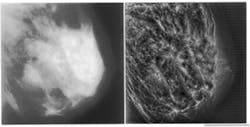

Detection of early malignancies while they are still small is problematical, especially in younger women who have denser breast tissue, because of the minor difference in x-ray attenuation between normal glandular tissues and malignant disease (see Fig. 1, left). Although calcifications present with malignancy may have high inherent attenuation properties, their small size also results in a low subject contrast. As a result, tumor detection will always be difficult in mammography done with analog film or screen imaging. Because mammograms display only about 3% of the information they detect, improvements in detection of small tumors and microcalcifications are more likely to occur by improving the visibility of these features.

With mammographic feature analysis via multiresolution representations, highly detailed image reconstruction is possible. Multiscale wavelet representations suggest a mathematically coherent basis not only for using existing multigrid techniques, but also for exploiting nonlinear systems. Multiresolution wavelet analysis provides a natural hierarchy that can contain pattern-analysis protocols for accomplishing feature analysis in scale-space, which is an imaging hierarchy of multiple scales. As with traditional coarse-to-fine matching strategies, the radiologist may first choose to look for coarse features, such as dominant masses, within low-frequency levels of the wavelet transform. Finer features, such as microcalcifications, can then be examined at higher frequency levels (see Fig. 1, right).

FIGURE 1. Lack of contrast makes dense-tissue mammograms particularly difficult to diagnose (left); image gains in contrast after global wavelet processing for four levels of analysis (right).